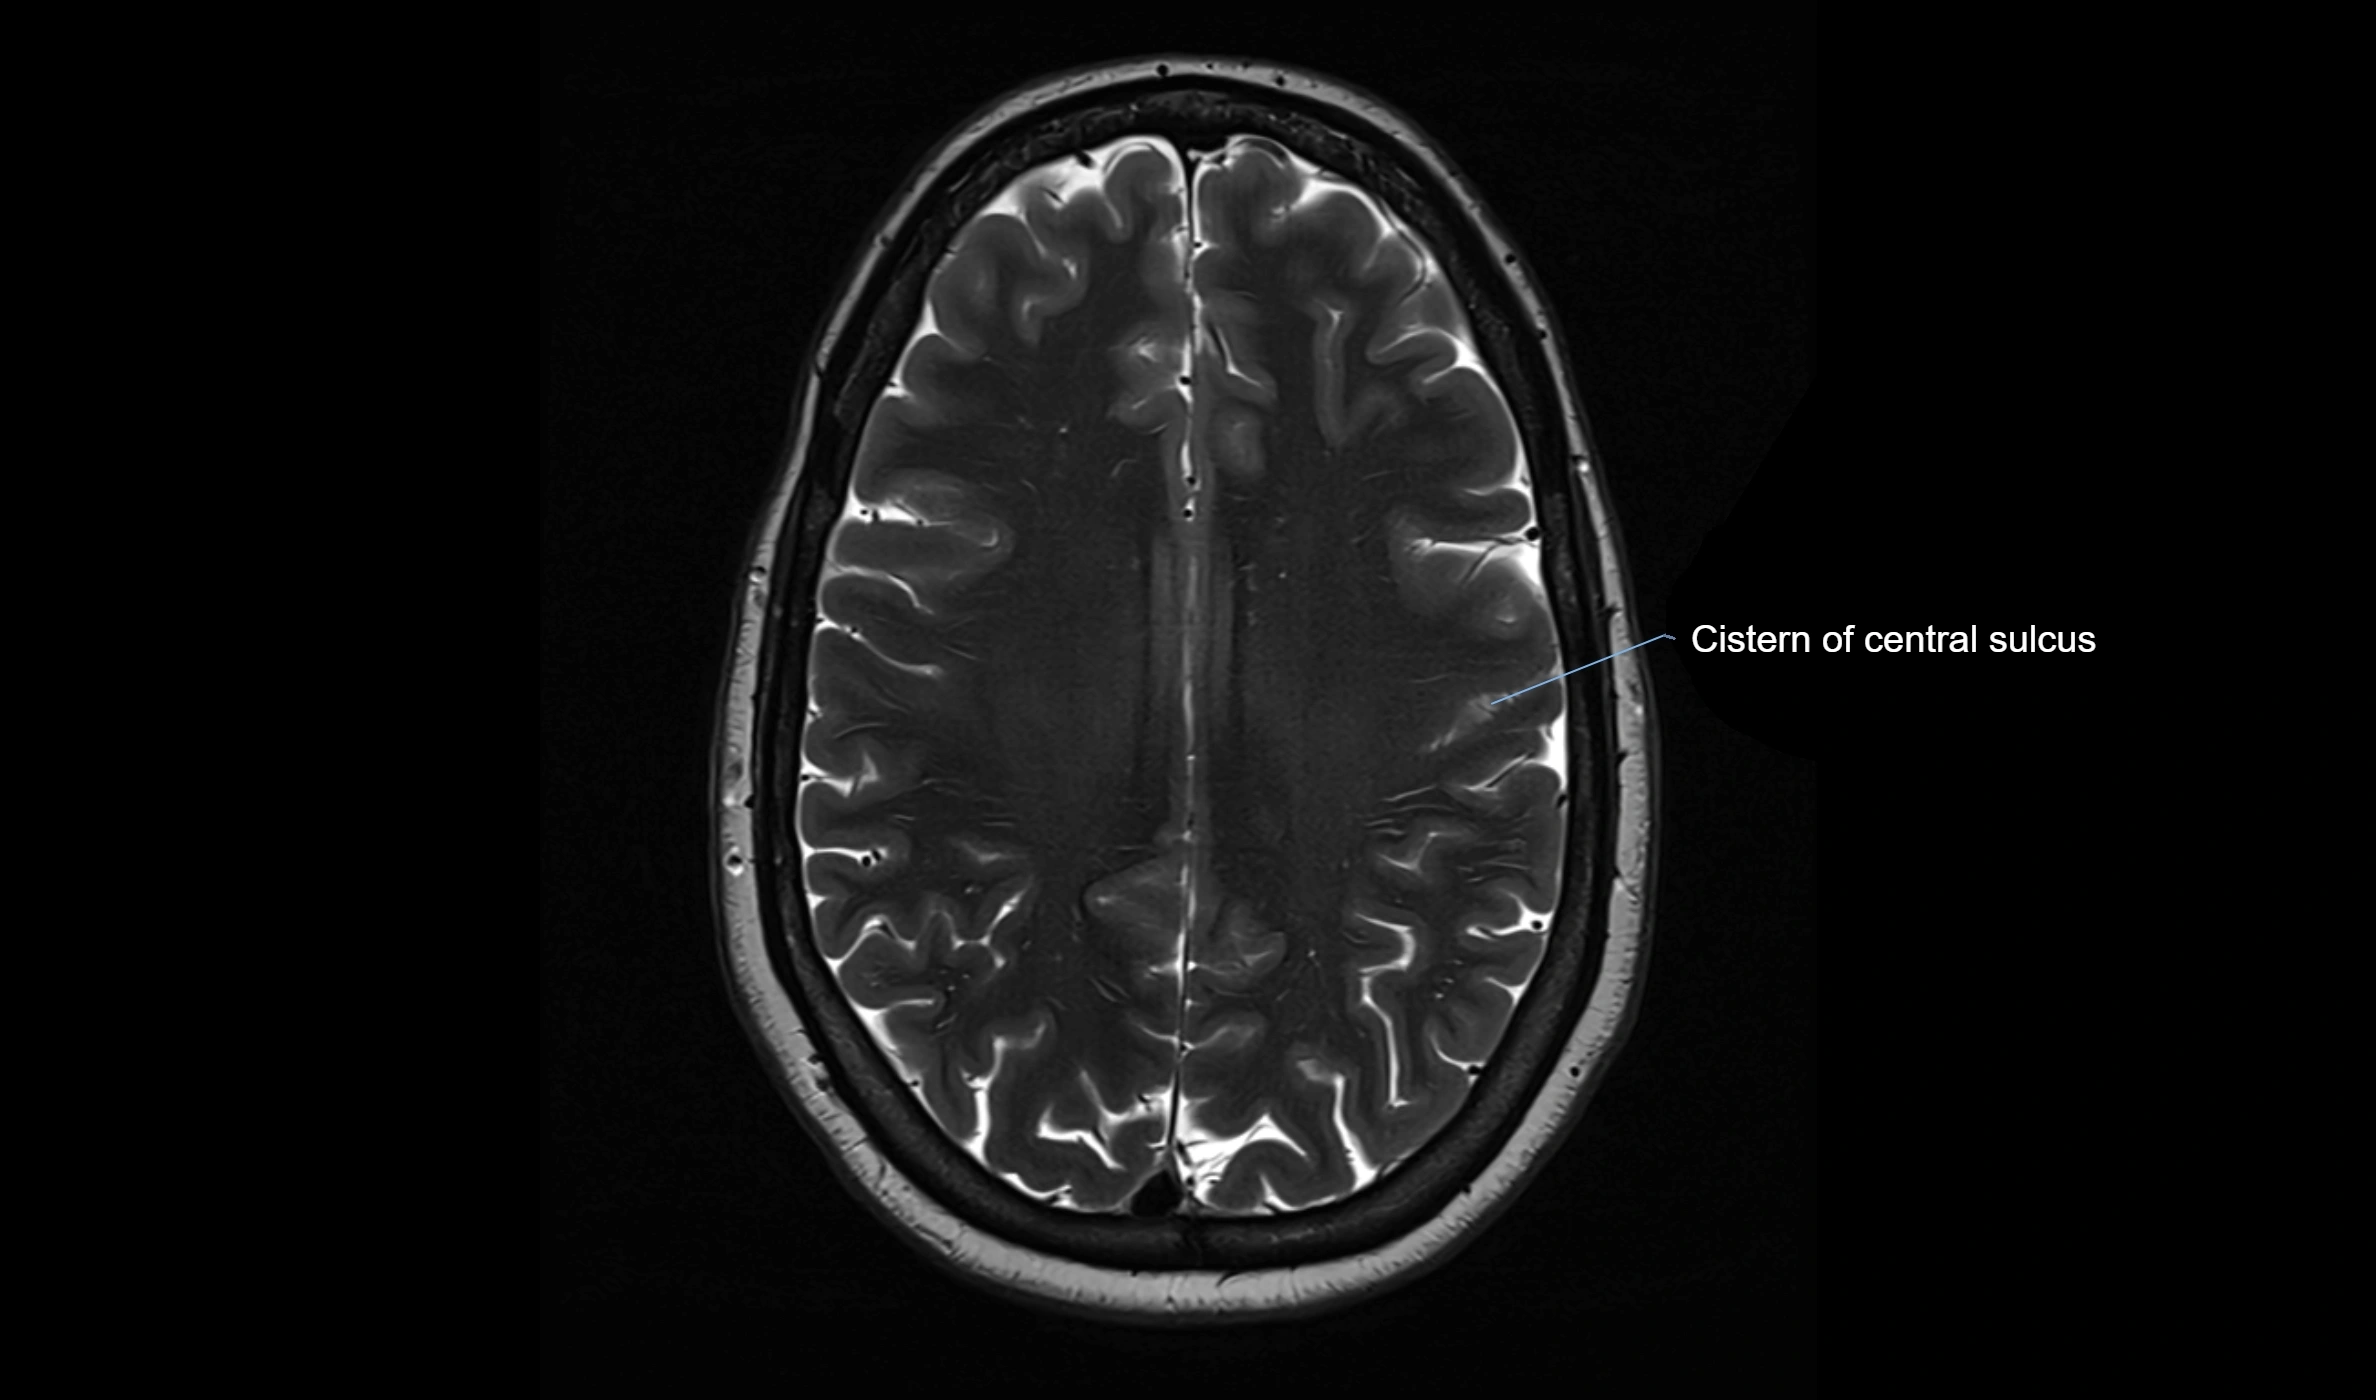

• T2-weighted images:

• The cistern is hyperintense (bright) due to the high water content of CSF.

• Encapsulated vessels and nerves are seen as flow voids or hypointense lines within the bright background.